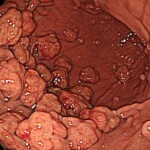

@PPIによって増大した胃底腺ポリープ